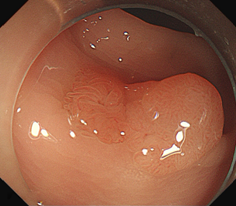

5、息肉大于2cm的息肉,要排除有无癌变可能,有无往更深的肌肉层生长。

肠息肉切除后会不会复发?

大肠息肉摘除术后很容易复发。大约有50%的大肠息肉患者在术后4年内出现了息肉复发。

肠息肉切除后,导致肠道长息肉的原因或环境没有改变,这片"土壤"还是容易滋生息肉的。

因此如果肠镜检查发现有息肉,虽然予以切除术,患者千万莫大意,仍要定期复查,尤其是息肉数目较多、息肉大、腺瘤性息肉者更要复查。